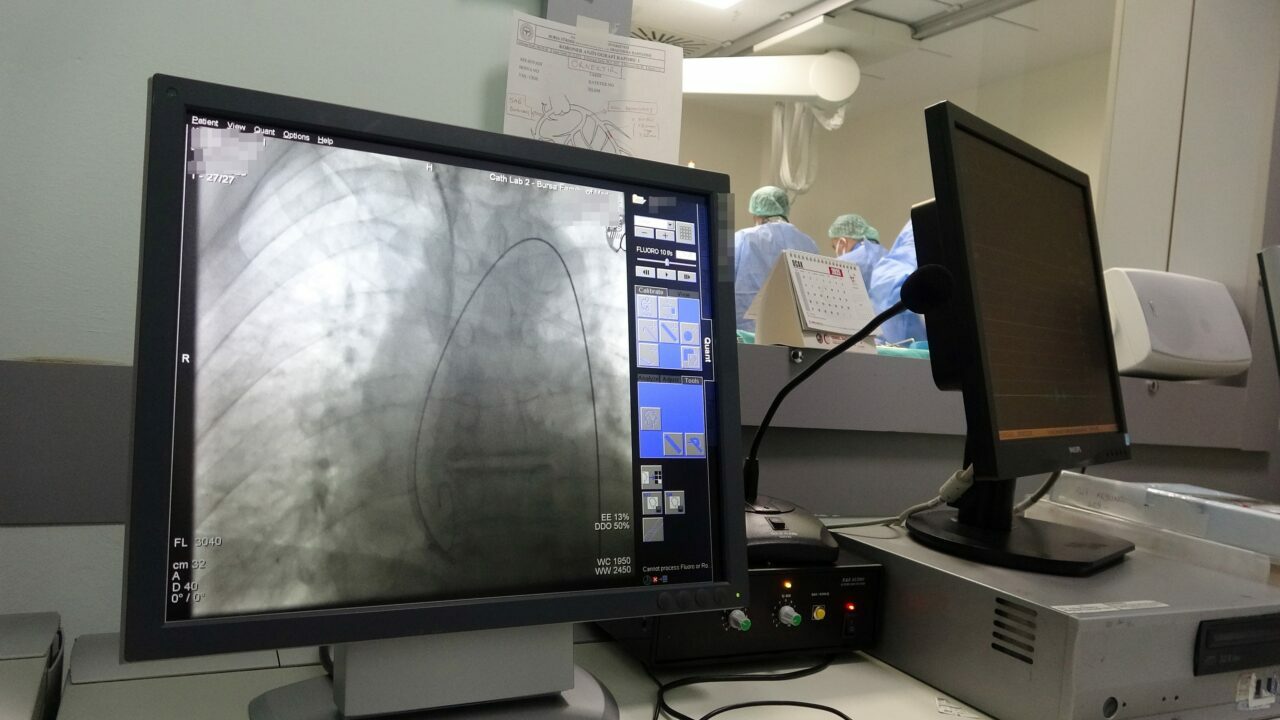

“Hastanemiz kardiyoloji ve kalp damar cerrahisi birimleri, gerek sayısal gerekse niteliksel açıdan ülkemizin en önde gelen merkezlerinden biridir. 2024 yılı itibarıyla kardiyoloji polikliniklerimize yaklaşık 140 bin hastamız ayaktan başvurmuştur. 25 bin hastamıza gerek servislerde gerek yoğun bakımlarda yatakta tedavi hizmeti sunduk. 20 bin hastamıza kardiyak girişimsel işlemler gerçekleştirdik. 14 bin hastamıza anjiyo işlemi yaptık ve yaklaşık 5 bin hastamıza stent uyguladık. Ayrıca 1200 hastamıza baypas işlemi uyguladık. Hastanemizde 7 gün 24 saat hizmet veren 4 adet koroner anjiyografi birimi bulunmaktadır. Birim başına en fazla işlem yapılan hastanelerden biri konumundayız. Günlük yaklaşık 100 kardiyak girişim gerçekleştiriyoruz. 2025 yılı itibarıyla, 5’inci anjiyo birimimizi de hizmete aldık. Bu yıl itibarıyla Türkiye’de birim başına en fazla işlemi yapan sağlık kuruluşu olmayı hedefliyoruz.”

“Sağlık Bilimleri Üniversitesi Yüksek İhtisas Eğitim ve Araştırma Hastanesi Kardiyoloji Kliniği, 1992 yılından beri Bursa halkına hizmet vermektedir. Kardiyoloji kliniğimiz, Türkiye’nin en önde gelen kliniklerinden biridir. Kliniğimizde yılda yaklaşık 20 bin girişimsel işlem yapılmakta; 1250 primer PCI dediğimiz acil balon stent işlemi gerçekleştirilmektedir. Bunun dışında yılda yaklaşık 14 bin anjiyo, 5 bin elektriksel stent işlemi, 600 pil işlemi ve 550 EPS işlemi yapılmaktadır. Ayrıca yapısal kalp hastalıkları girişimleri kapsamında VSD, ASD gibi seçimsel işlemler de kliniğimizde gerçekleştirilmektedir. Kardiyoloji kliniğimiz, yaptığı işlem sayısı ve kalitesi itibarıyla Türkiye’de bu alanda söz sahibi kliniklerden biridir.”